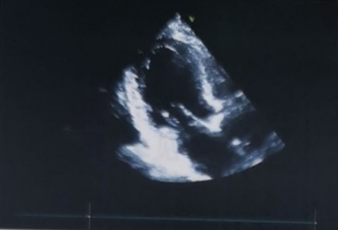

心脏彩超

峰值流速:5M/s

最高跨瓣压差:100mmHg

平均跨瓣压差:67mmHg

左室射血分数EF值:50%

左室舒张末期内径(LVD):58mm